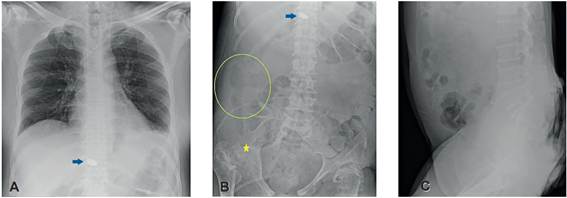

Figura 2.

A y B. Tomografía computarizada de abdomen y pelvis donde se aprecian la colección multiloculada (estrella amarilla) localizada en la gotera parietocólica, que se extiende hasta la región perihepática entre el segmento VI y el diafragma, compromete los tejidos blandos de la pared torácica posterolateral, con extensión entre el aspecto inferior del músculo latísimo del dorso, el cuadrado lumbar y el erector de la espina, en el sentido inferior se extiende hasta la fosa ilíaca derecha, se encuentra en contacto con la pared lateral del colon ascendente y los músculos oblicuos, mide 20 x 8 x 6 cm en los ejes longitudinal, anteroposterior y transverso respectivamente, con volumen calculado de 500 ml. C y D. Además, se visualiza el extenso proceso inflamatorio que compromete los tejidos blandos de la región sacra, perineal y el ano, con aumento difuso y heterogéneo en la densidad del tejido celular subcutáneo e irregularidad de la dermis, y en la unión posterior de la articulación sacroilíaca derecha (flecha azul), se observa defecto en la continuidad de los tejidos blandos, la cual probablemente esté comunicada con la colección en la gotera parietocólica ipsilateral.